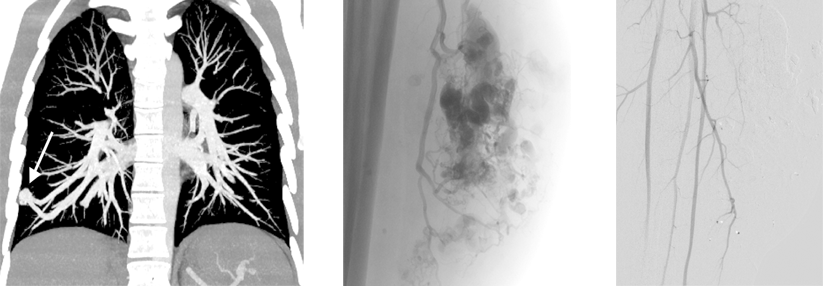

Trotz der modernen diagnostischen und therapeutischen Möglichkeiten sehen die Prognosen bei chronisch-ischämischen Herzkrankheiten oft schlecht aus. Trotz der modernen diagnostischen und therapeutischen Möglichkeiten sehen die Prognosen bei chronisch-ischämischen Herzkrankheiten oft schlecht aus. © Pixabay und wikimedia/Patrick J. Lynch (CC BY 2.5)